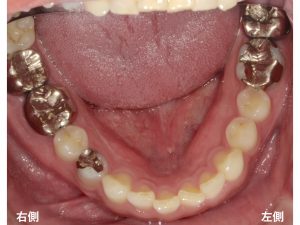

以下が初診時です。

患者様は、口腔内全体の金属を除去したいとの希望で来院されました。

まず最初に

右下の奥歯の2歯の金属を除去して、

金属を一切使用しないオールセラミックを行うことになりました。

右下一番奥歯は、親知らずで

奥から2番目と3番目が治療対象です。

奥から2番目は、ジルコニアオールセラミック

奥から3番目は、e.max オールセラミック

で治療を行います。

以下が治療後です。